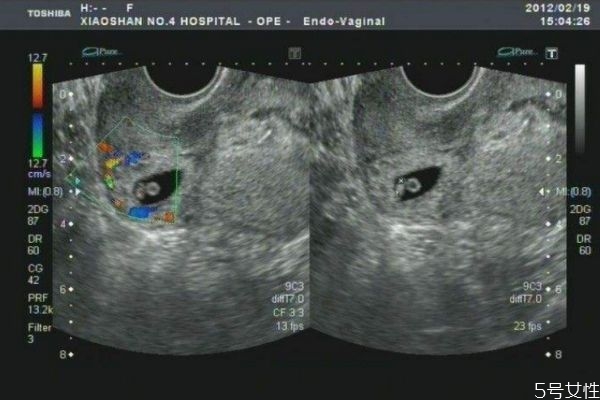

疤痕子宮就是說子宮已經(jīng)有疤痕,也就是說子宮已經(jīng)有過手術(shù)治療,比如子宮肌瘤的挖除,還有剖腹產(chǎn)的手術(shù),這些都是疤痕子宮。

越來越多的瘢痕子宮選擇再孕,這在一定程度上增加了妊娠并發(fā)癥和并發(fā)癥的風(fēng)險,前置胎盤上的子宮結(jié)合疤痕正在增加。過去四年中,危險胎盤顯著增加,比2008年前增加了五倍。子宮切除術(shù)的比例增加了4倍。據(jù)報道,剖腹產(chǎn)后,前置胎盤的風(fēng)險從0.38%增加到0.63%。當(dāng)?shù)谌螒言袝r存在前置胎盤時,胎盤植入物的風(fēng)險增加40%。子宮疤痕復(fù)發(fā),子宮破裂發(fā)生率約為1%。報告顯示,過去8年,婦女再次懷孕,有10例完全性子宮破裂,其中大部分為子宮肌瘤病史。只有一例涉及剖宮產(chǎn),有子宮肌瘤的拒絕史發(fā)生子宮破裂。破裂不是在先前的剖腹產(chǎn)疤痕處,而是在纖維瘤部位。因此瘢痕子宮的婦女雖然可以懷孕,但是面臨著重大的風(fēng)險。